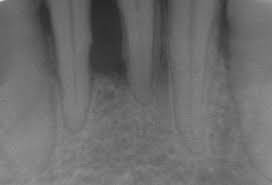

If youve followed excellent oral hygiene at home and maintained regular dental visits but still have serious gum periodontal disease you may have a hereditary tendency toward it. Aggressive periodontitis for example a relatively uncommon disease which causes rapid bone loss around certain teeth is often more common among members of the same family. One half of these individuals will develop the advanced stages of periodontal disease.

A genetic perspective Periodontitis is a multifactorial disease that causes tooth loss. If youve followed excellent oral hygiene at home and maintained regular dental visits but still have serious gum periodontal disease you may have a hereditary tendency toward it. Many oral health conditions have a hereditary basis. 36 years experience ENT and Head and Neck Surgery. The molecular abnormality and its genetic inheritance has been established in some cases of generalized prepubertal periodontitis. Studies have shown that periodontal disease appears to have some kind of genetic component especially for serious diseases and those that appear early in the patients life. Many studies have provided a valuable contribution to understanding the genetic basis of periodontal disease but the s. 38 linhas EDS type VIII is the rarest form of EDS and is characterized by severe early. On the other hand the genetics of susceptibility to inflammatory periodontal diseases.